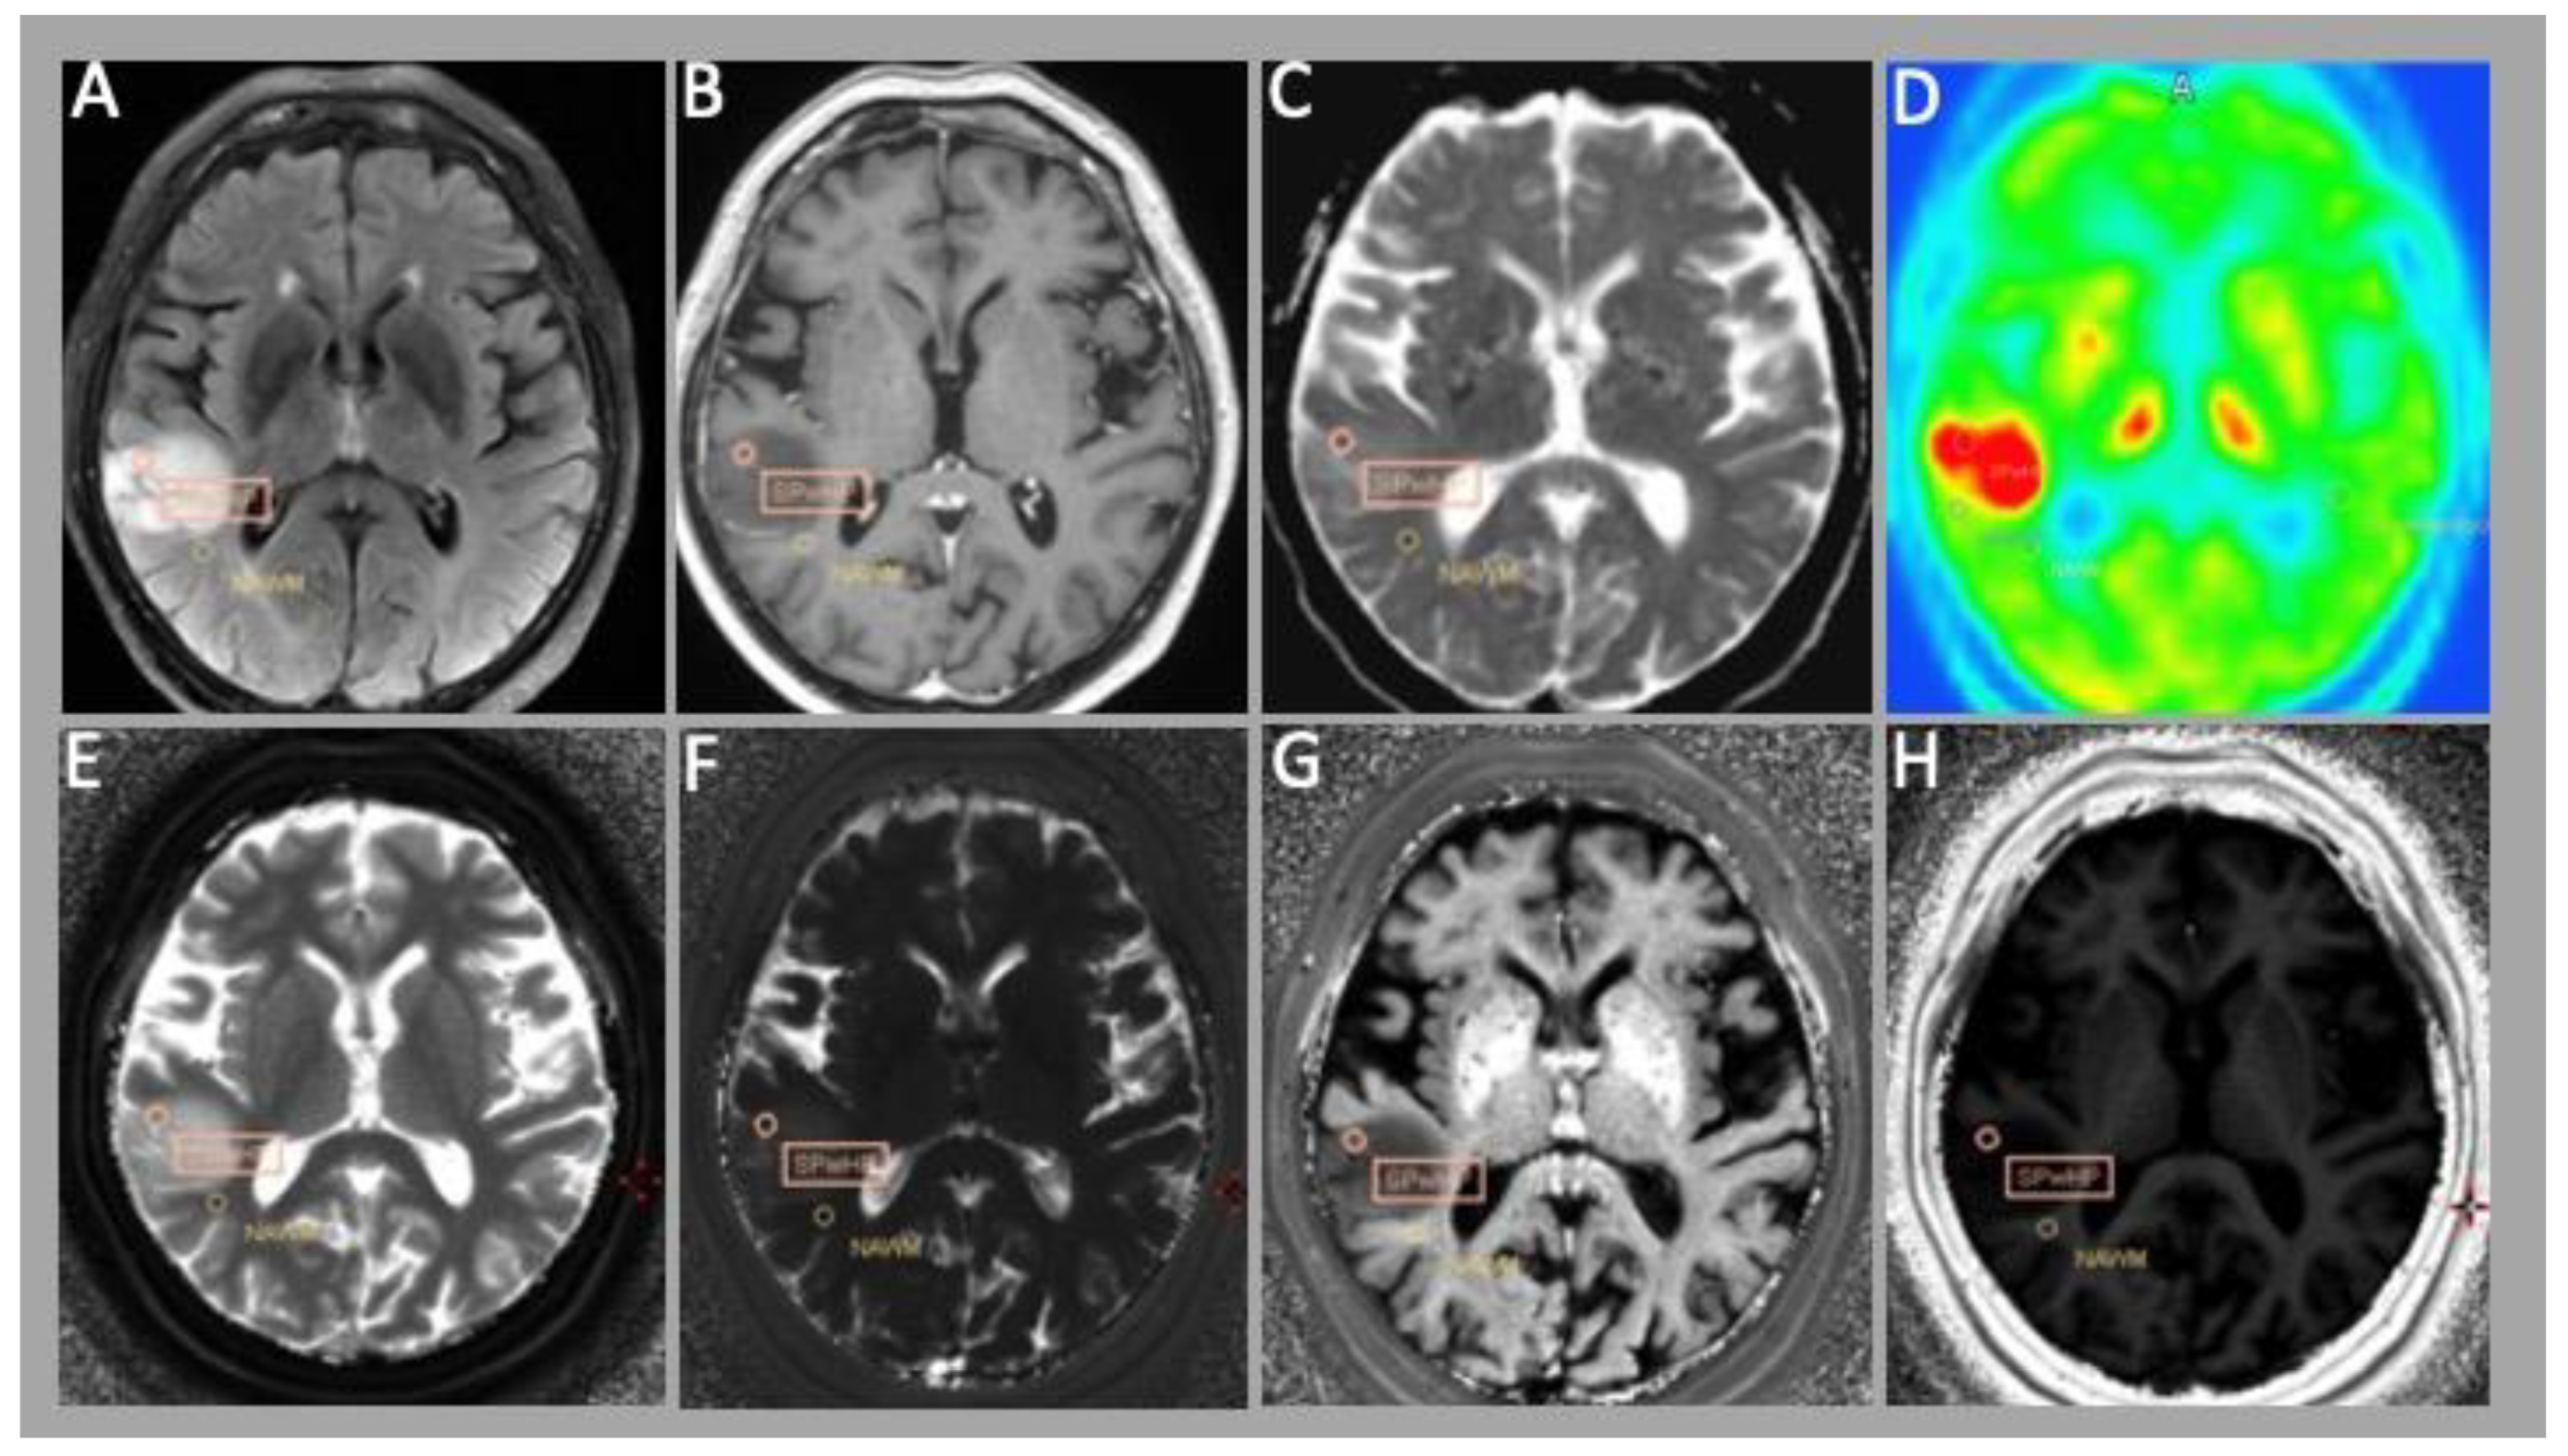

3.1. MRF

3.2. PET Evaluation

3.3. Correlation of MRF and PET